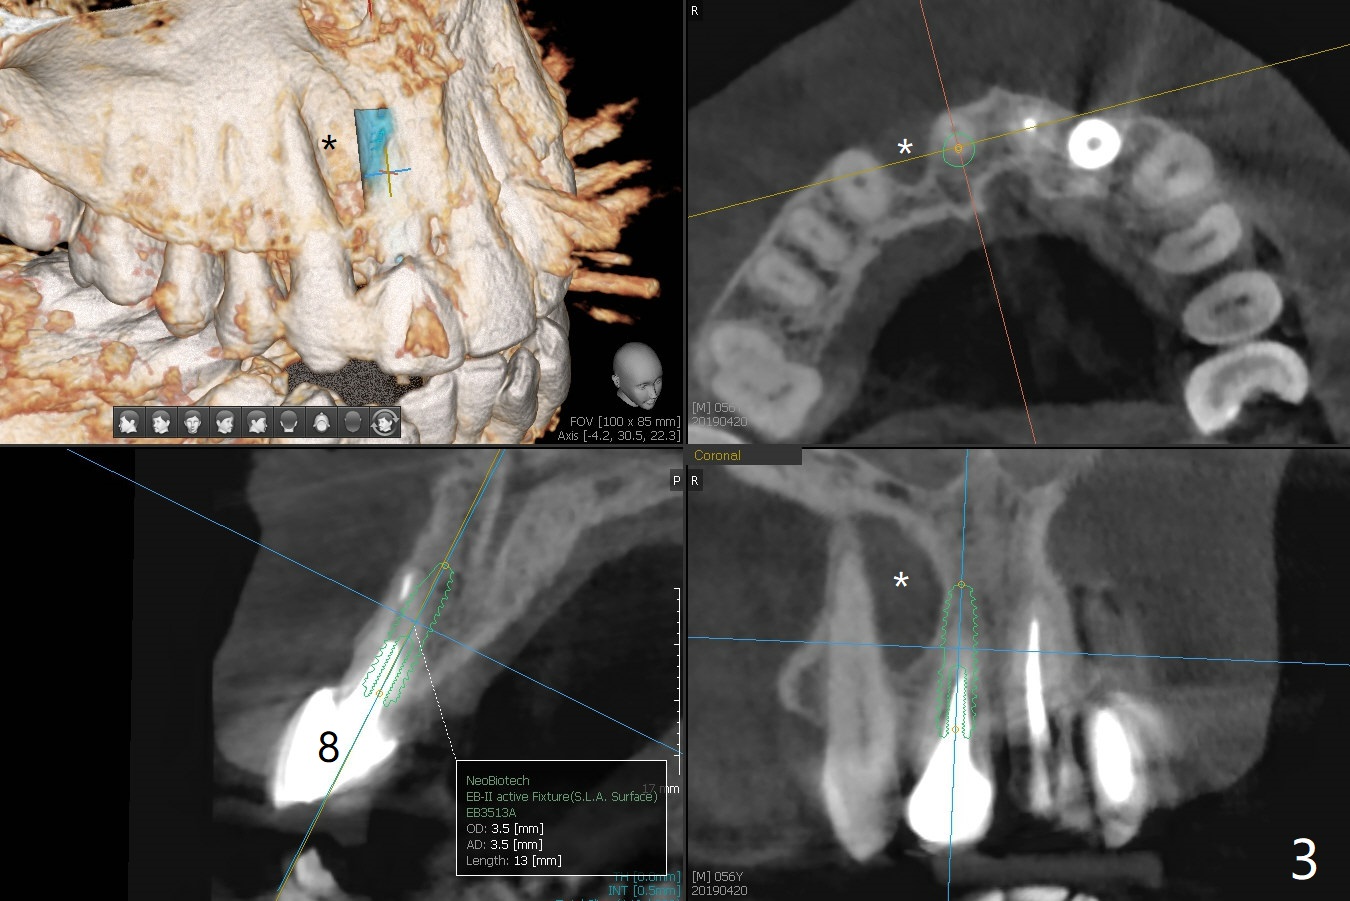

A 56-year-old man presents to clinic for recementation of the crown/post at #8, which is non-salvageable (Fig.1). There are 3 existing implant crowns, including #10. The implant at #10 (4.5 mm in diameter) was placed buccally, although there is no infection (Fig.2). To prevent this complication, a smaller implant should be placed palatal (Fig.3). In addition, the tooth #7 is missing. Instead there is a labial concavity (Fig.3 *). Use a temporary abutment for provisional.